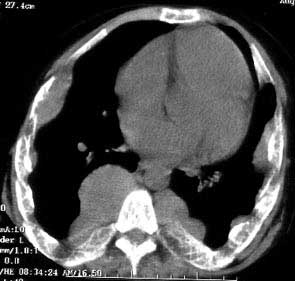

以下是引用jiajie在2004-12-10 22:14:53的发言:[br]多发性肋骨骨质疏松,[br][br]麦粒状及筛孔状骨质破坏,[br][br]髓腔膨胀皮质变薄,[br][br]骨旁多发软组织肿块,[br][br]考虑恶性病变,支持肋骨多发性骨髓瘤。

以下是引用pujunzhi在2008-7-3 21:21:00的发言:[br]支持地中海贫血伴髓外造血可能性大,需与多发性骨髓瘤、淋巴瘤等鉴别。